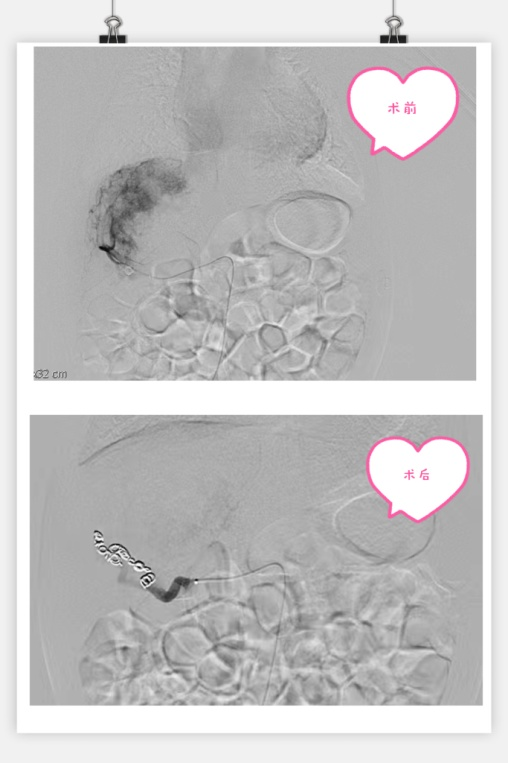

3月13日,在小儿外科高亚教授、郑百俊教授及郭新奎教授及多学科的积极配合下,为患儿进行了肝动脉造影术+肝动脉栓塞术。新生儿股动脉纤细,常规股动脉鞘作为入路存在术后股动脉闭塞下肢缺血风险,采用了经股动脉单纯微导管超选择性栓塞,手术难度大大增加,但避免了股动脉缺血风险。

在麻醉科(吴刚副主任,罗倩倩、陈趟医生)和新生儿科(王惠萍教授、王莉医生)的保驾护航下、超声科(何鑫医生)的精准定位置管,血管介入团队(彭玉萍教授、刘强教授、杨晓东医生)经过3小时的努力,共封堵四处肝血管瘤的主要供血动脉分支,手术过程患儿生命体征稳定,血管瘤的血流量逐渐减少,进行心功能测定显示心输出量较术前下降,效果显著,肝脏的“扫雷”行动获得阶段性的成功,在场的所有医务人员为孩子鼓掌加油!